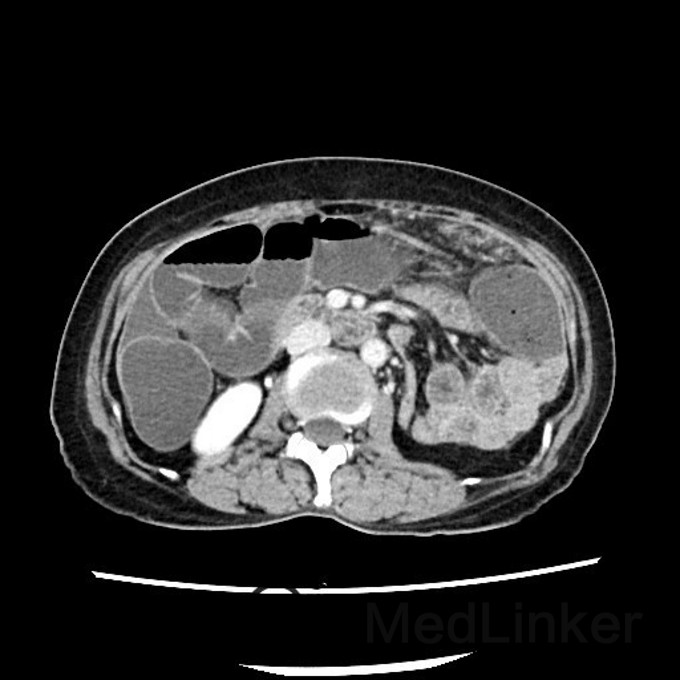

问题:患者女,50岁,因腹胀而就诊,遂行胸腹CT,提示:腹部大网膜、小网膜区脂肪间隙模糊,腹膜增厚,可见片絮状、小结节状软组织密度影,增强扫描见轻度强化。考虑转移癌可能性大。后行大网膜活检,病理结果提示:低分化转移癌。但全身PET/CT未见原发灶,此种情况下,常考虑原发灶在那些部位,以及进一步做什么检查?